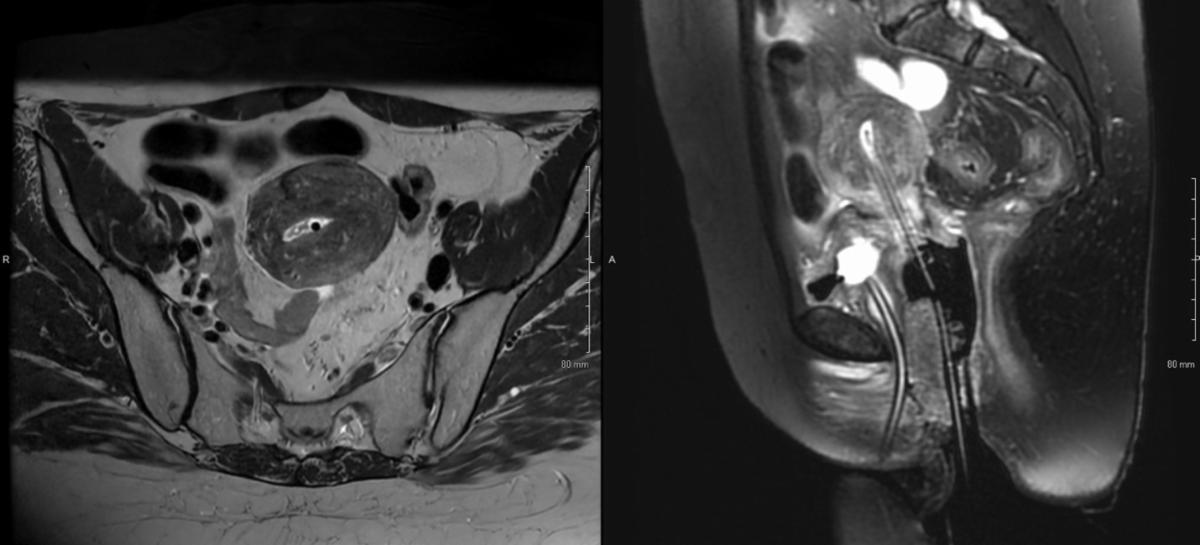

For the second fraction, due to uterine size and myometrial involvement, a 3 cm Rotte-Y applicator was used instead of a uterine tandem. Interstitial needles were omitted to minimize risk of bleeding and tissue damage, and the fact that there was no significant residual parametrial disease. The dual tandems of the Rotte Y applicator were rotated into position, and secured together, confirmed with ultrasound. Similar to fraction #1, 25 mm MRI/CT-compatible ovoids were selected and assembled onto colpostats. The ovoids/colpostats were advanced into the vaginal fornices, and the 2 tandems of the Rotte Y were centered between the ovoids. The colpostats were secured together with a simple bridge. A rectal paddle was placed under the ovoids. Wet Kerlix gauze packing was placed to help displace the bladder and rectum and to secure the applicators. The Rotte Y applicator and the colpostats were secured together with foam tape. Since Rotte-Y applicator is not MRI-compatible, she underwent high-quality CT to be used for planning and reconstruction, and were fused to the MRI from her fraction to assist with GTV and HR-CTV delineation. This plan proved to be dosimetrically superior with improvement in HR-CTV V90% (91.5% to 97.8%), HR-CTV D90 (6.5 to 7.4 Gy, 13.9%), HR-CTV D98 (5.1 Gy to 6.3 Gy, 23.5%). This was also associated with improvement in bladder (-9%), bowel (-10.9%), and rectal (-1.3%) D2cc, though with increase in sigmoid dose given the anatomy that day (+14.4%).

Given optimal dosimetry and target coverage, customized Rotte-Y/ovoids/colpostats applicator set was used for subsequent fractions. Figures 4A-B summarize fraction by fraction change in target coverage and OAR doses, with specific doses listed in Table 1. She tolerated treatments exceptionally well with no apparent procedural complications.

Figure 3B-E: HDR-BT Fraction 1 MRI in MIM treatment-planning software